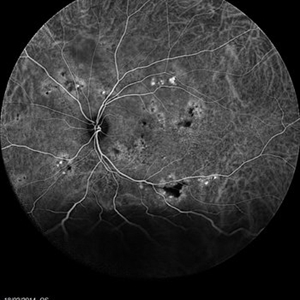

Multifocal Exudative Detachments Due to VKH

May 14 2014 by Avris Romario Diparaja Siahaan

FA a 38-year-old man with multifocal CSR and inferior exudative retinal detachment on both eyes (Harada Syndrome).

Photographer: Avris Romario Diparaja Siahaan, Klinik Mata Nusantara

Imaging device: Heidelberg HRA + OCT Spectralis

Condition/keywords: multifocal central serous chorioretinopathy (CSCR)